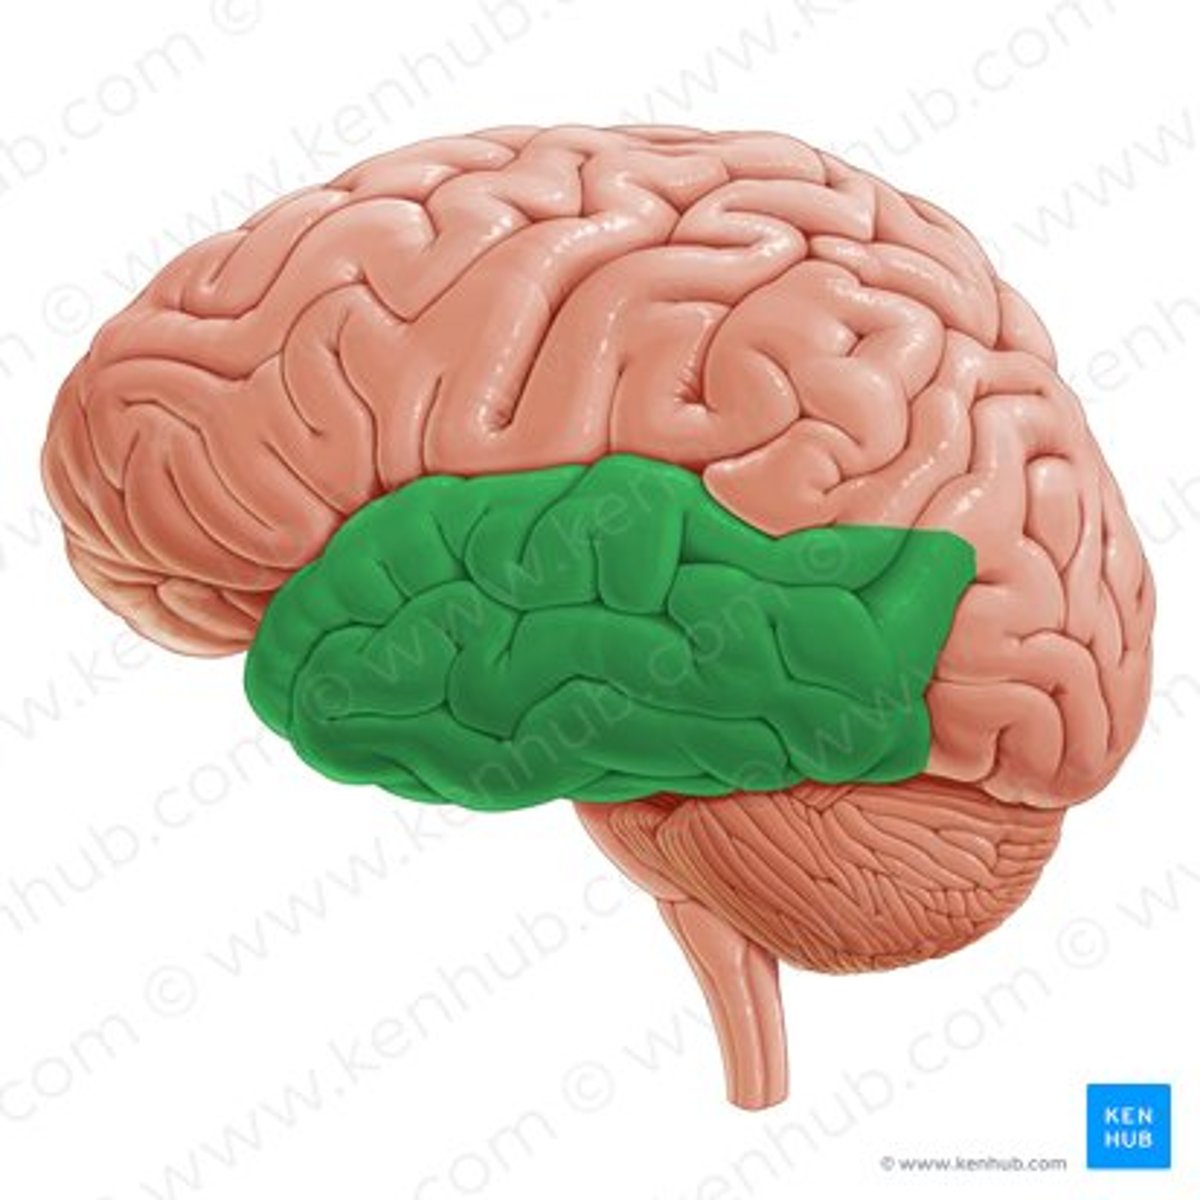

temporal lobe